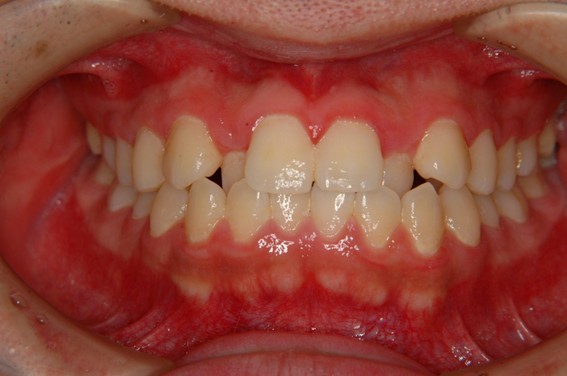

| 主訴 | 前歯が逆に噛んでいる。 |

| 治療内容 | 表側ワイヤー矯正、ジルコニア補綴を行いました。 |

| 治療費 | ワイヤー矯正660,000円(税込) ジルコニア176,000円(88,000円×2歯)(税込) |

| 治療期間 | 30ヶ月 |

| 治療回数 | 30回 |

| 想定されたリスク | 歯根吸収、歯髄壊死、歯髄充血、歯肉退縮のリスクがありました。 |

骨格性Ⅲ級・前歯部反対咬合の症例でした。反対咬合のまま治療していた前歯のサイズ不調和を、表側ワイヤー矯正とプロビジョナルクラウンで調整。正中を整え、犬歯・臼歯ともⅠ級、適切なオーバージェット(上下前歯の前後的な距離)・オーバーバイト(上下前歯の垂直的な重なり)に仕上げました。